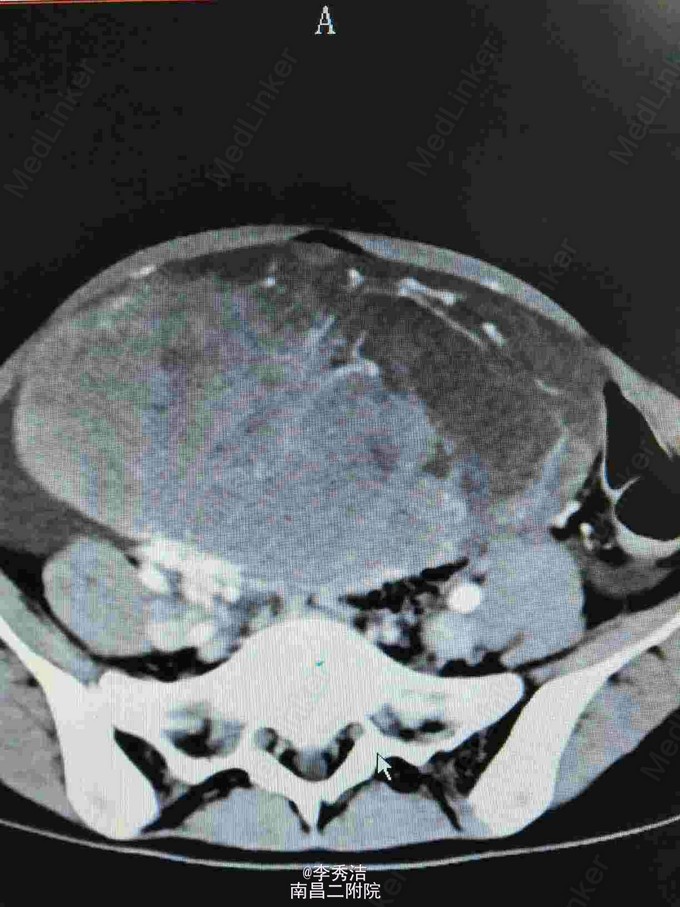

查体:中下腹部明显彭隆,未见肠型及蠕动波,未见腹壁静脉曲张,腹肌软,下腹部可触及约20*20cm包块,质硬,活动度差,叩诊实音,肝脾肋下未及,妇科检查:外阴:已婚未产式;阴道:畅软,少量白色分泌物;宫颈:少糜,宫体及双附件因盆腔巨大包块扪诊不清。血清HCG70.1mIU/ml。腹部CT示腹盆腔内见一巨大包块影,大小约16*8.1cm,增强扫描示不均匀增强,腹腔、盆腔内见积液,结合血清HCG,不排外生殖系统恶性肿瘤可能。彩超示:子宫上方巨大包块,不排除来源于附件可能,子宫、显示不清。双侧附件

诊断:腹腔包块性质待查,在全麻下行剖腹探查术,腹腔见淡黄色腹水约100ml,子宫色泽及形态无异常,左侧附件无异常,右侧卵巢见一大小约30*25cm囊肿,右侧输卵管附着于包块上,大网膜见两个绿豆大小结节,包块表面见血管丰富,术中出血较多,遂行右侧附件切除。送术中冰冻示:无性细胞肿瘤,考虑患者处于Ia期, 遂行双侧附件切除+双侧盆腔淋巴结清扫+大网膜切除术,手术顺利。术后诊断:卵巢无性细胞瘤 Ia期。